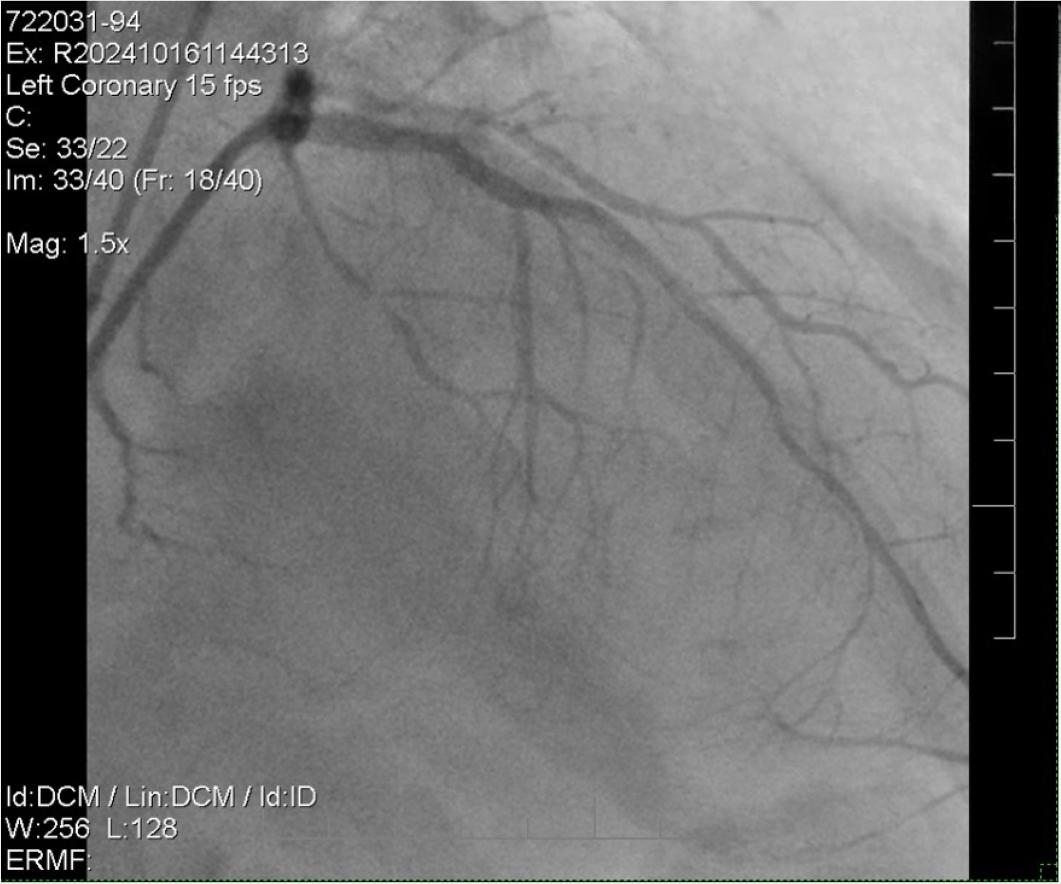

Twelve days later, the patient reported persistent angina symptoms and underwent further intervention for the coronary lesion. During the procedure, a guiding JR catheter, followed by an AL1 catheter, was used to advance a Fielder XT guidewire across the distal left anterior descending (LAD) lesion. Lesion preparation was performed using a Sapphire II Pro balloon (1.0 × 15 mm) to dilate the LAD II stenosis. However, despite balloon angioplasty, significant residual stenosis (approximately 80%) persisted, necessitating the deployment of a Combo Plus drug-eluting stent (DES) measuring 2.5 × 33 mm.

Attempts to intervene on the right coronary artery (RCA) using Runthrough, Fielder XT, and Gaia 1 guidewires with microcatheter support were unsuccessful, as the wires failed to cross the proximal stenosis. Consequently, the decision was made to address the proximal LAD lesion, where an additional Combo Plus DES (2.75 × 33 mm) was deployed. Post-stent placement, follow-up imaging confirmed TIMI 3 flow, indicative of successful revascularization (Figure 3).

LAD intervention